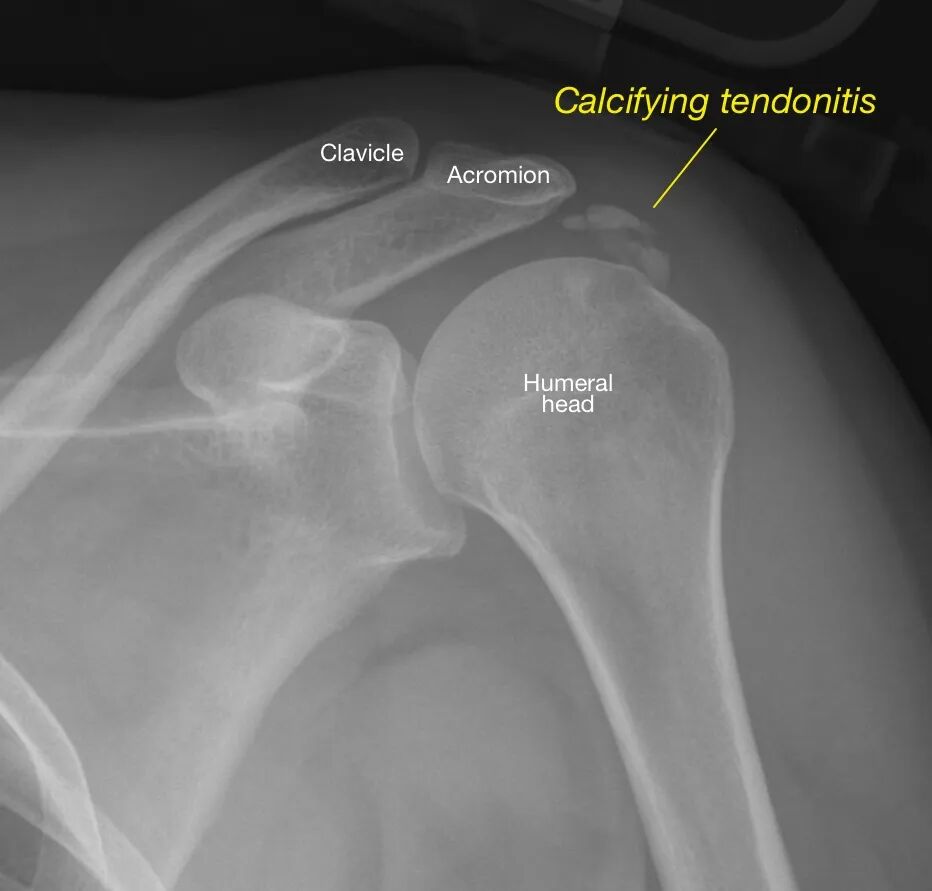

錯誤(C) 急性鈣化性肌腱炎(acute calcific tendinitis)

鈣化組織,在X光上看的到

C:鈣化性肌炎肌腱會照到白色的

圖片來源:https://radiopaedia.org/cases/adhesive-capsulitis-frozen-shoulder-3、https://bmjopenquality.bmj.com/content/9/1/e000550、https://shoulderelbow.org/2016/11/21/calcific-tendinitis-calcifying-tendonitis/、https://universityorthopedics.com/what_hurts/shoulder_arthritis.html